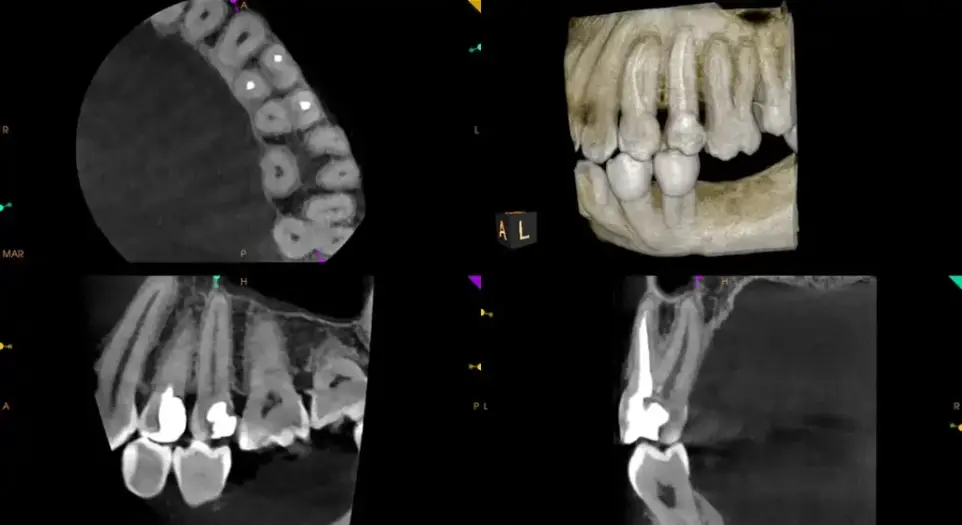

Enhanced Diagnostics

Capture detailed 3D images of teeth, bone, nerves, and soft tissue—seeing what traditional X-rays often miss. Perfect for identifying complex issues early.

Personalized Treatment Planning

Each scan provides precise data for implants, root canals, TMJ therapy, or orthodontics, ensuring accuracy and comfort from day one.